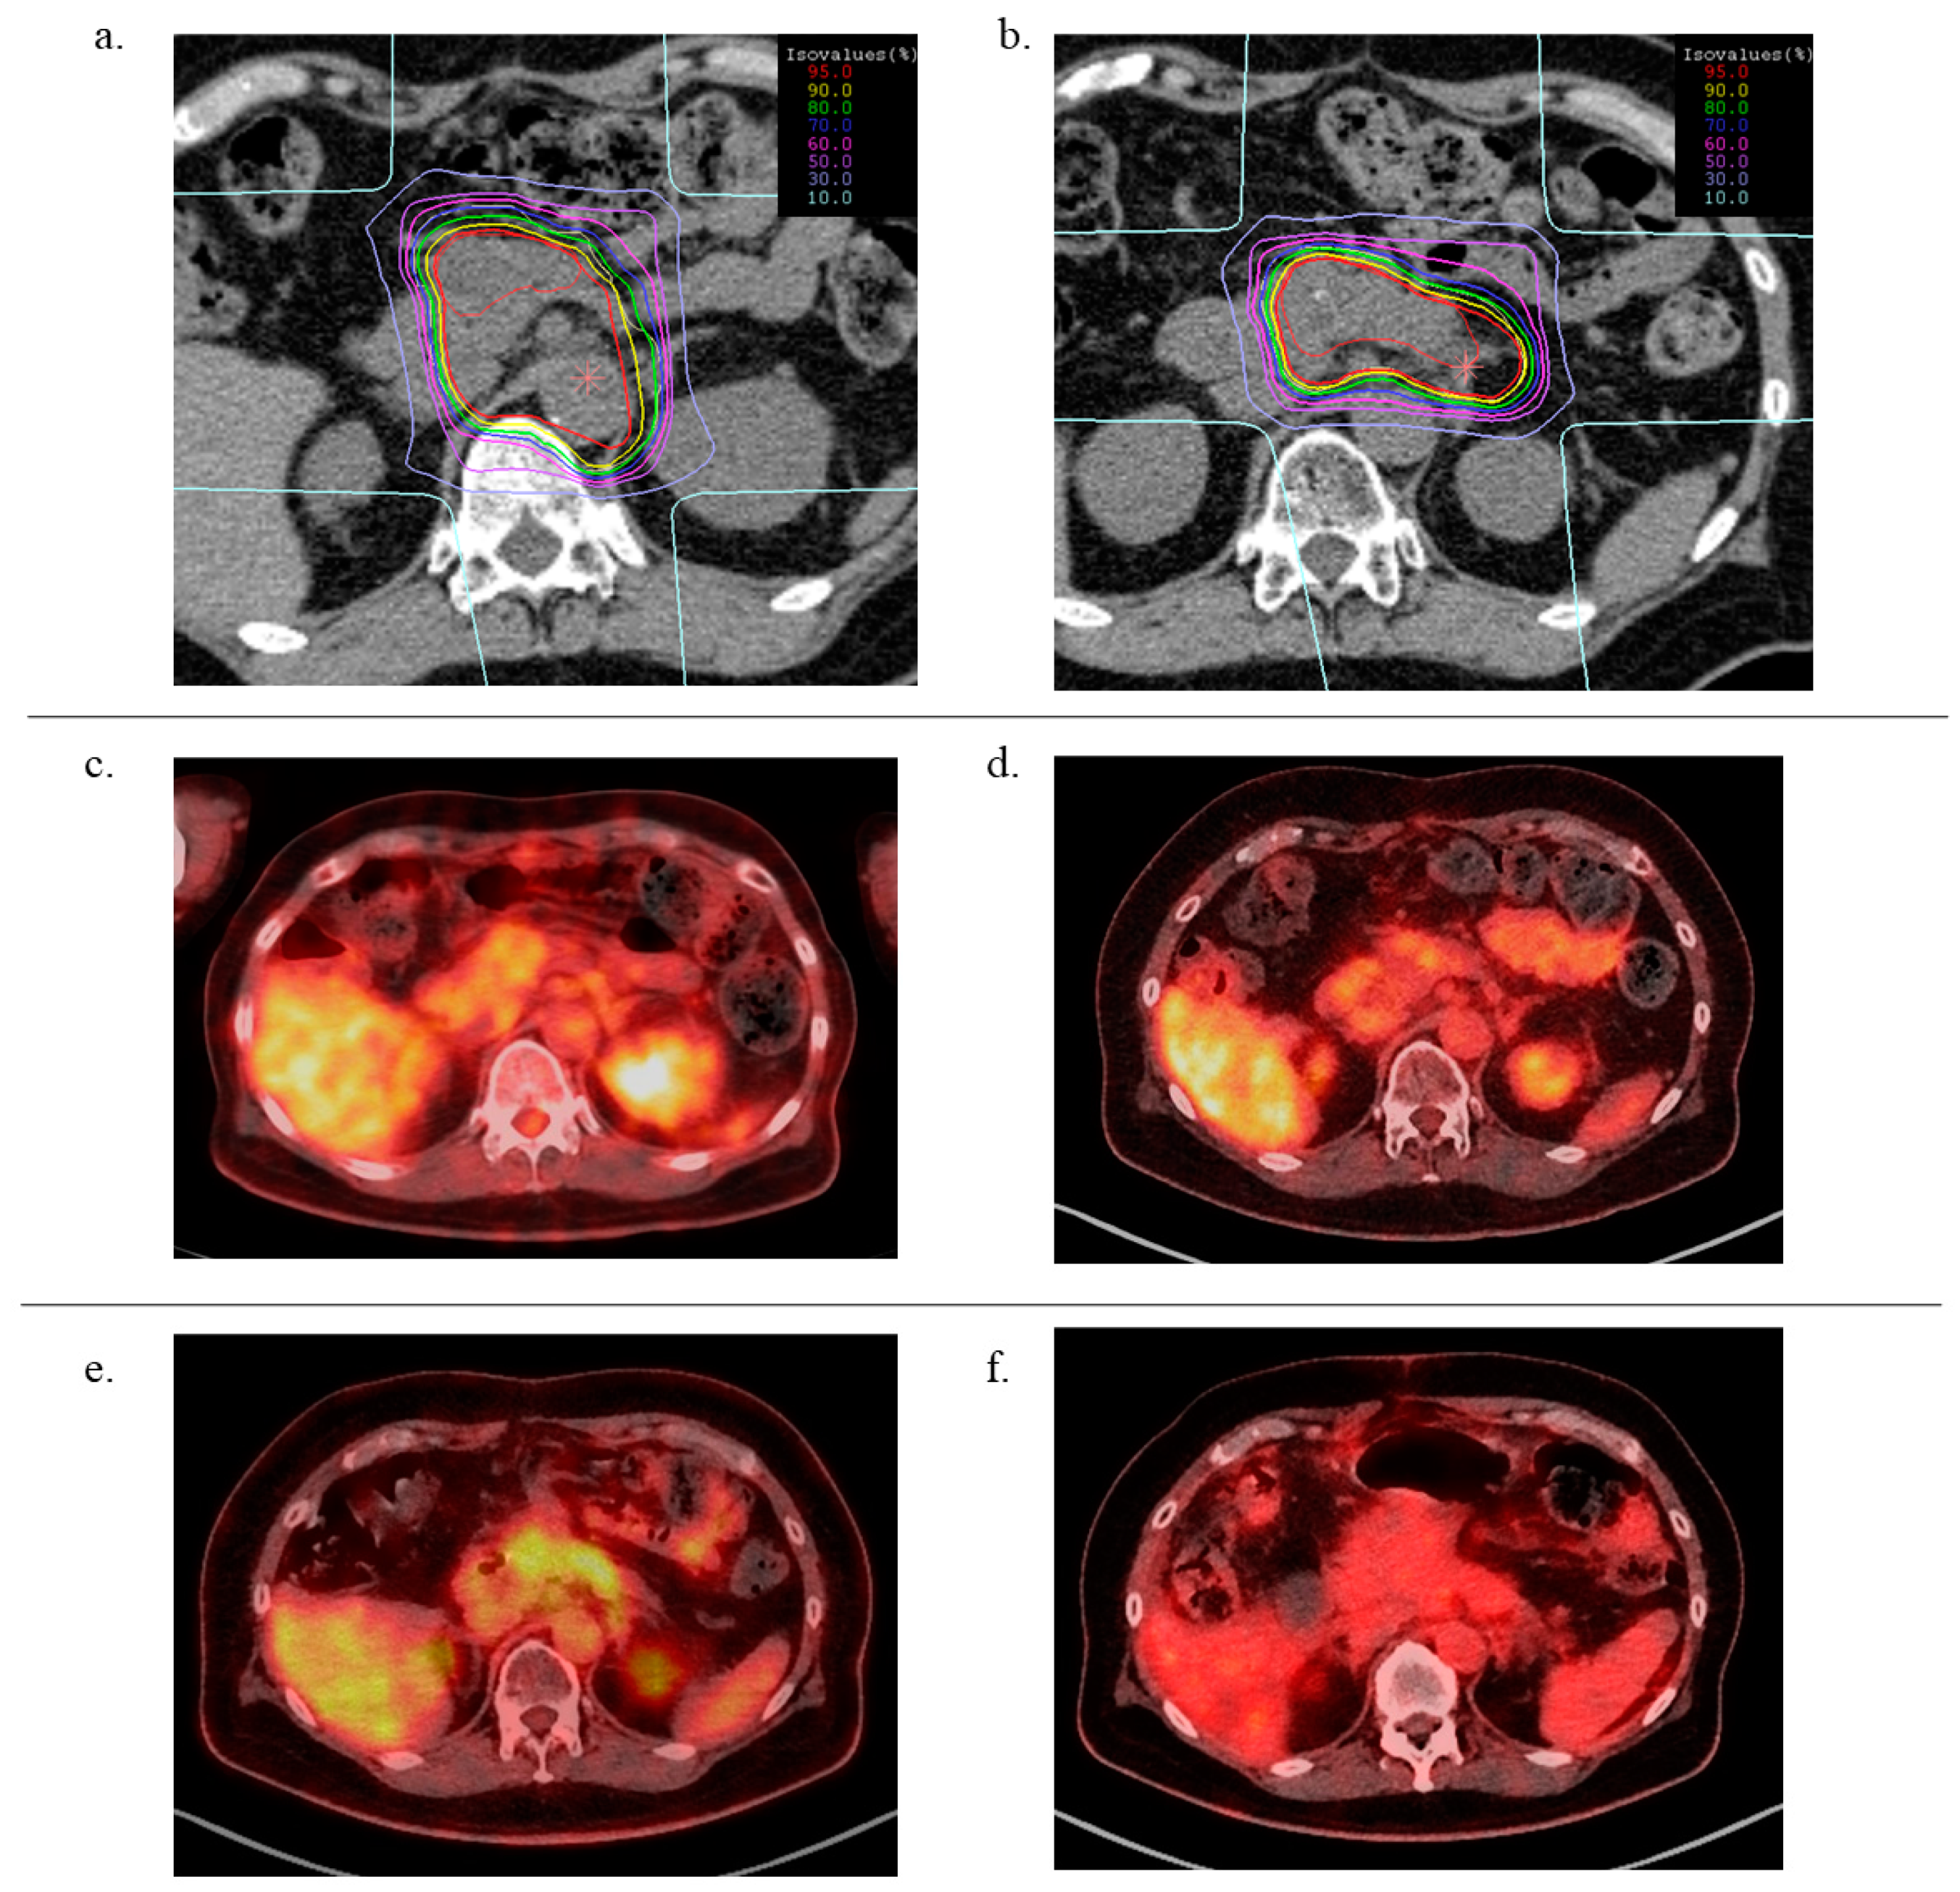

A typical case (patient #8) is shown in Figure 1. The dose distribution of 1st CIRT indicates that the prophylactic lymph node lesions (such as the para-aortic area) were irradiated during the initial CIRT. Conversely, during the second CIRT, only the recurrent tumor was included in the clinical target volume (CTV). The FDG-PET/CT images showed that both the first and second CIRTs were effective in decreasing the standard uptake values of FDG 3 months after irradiation.

Figure 1.

Typical case presentation: 55-year-old female patient with pancreatic body cancer. (a) Dose distribution of 1st CIRT, (b) dose distribution of 2nd CIRT, (c) fluorodeoxyglucose (FDG)-positron emission tomography (PET) computed tomography (FDG-PET/CT) image before 1st CIRT, (d): FDG-PET/CT image at 3 months after 1st CIRT, (e): FDG-PET/CT image at the recurrence after 1st CIRT, (f): FDG-PET/CT image at 3 months after 2nd CIRT.